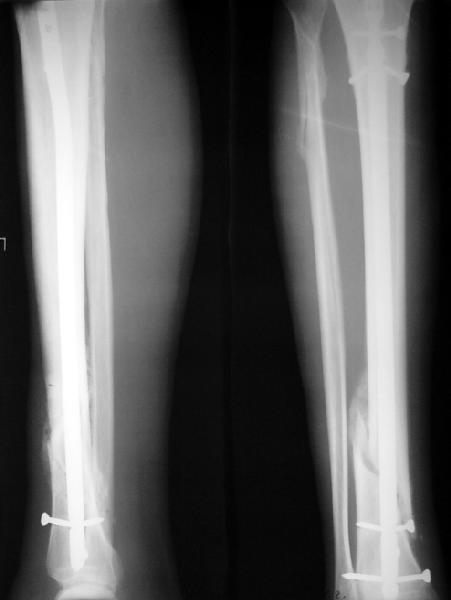

На мой взгляд, на снимках, приведённых Вами - неправильно сростающийся перелом дистальной трети большеберцовой кости, состояние после остеосинтеза интрамедуллярным гвоздём.

Как Вы пишите снимок под номером 1 - менсяц после операции, под номером 2- два месяца после операции.

Вы не послали послеоперационный снимок, поэтому трудно судить о состоянии редукции после операции.

Установка с медиальной стороны гвоздя в области дистального фрагмента дополнительного шурупа помогло бы Вам репонировать и удержать перелом в анатомическом положении, предотвратило варусную деформацию и смещение по ширине.

На мой взгляд внутрикостная фиксация переломов дистальной и проксимальной трети большеберцовой кости, за исключением поперечных, не очень хорошее решение вопроса, аппарат Илизарова или Тэйлора, позволяющие призвести закрытую анатомическую редукцию и отличное удержание отломков в период сращения.

Пример, приведённый Вами в нашей дискуссии по времени нагрузки после остеосинтеза не совсем удачный... Ваш больной имеет счастье, что первым согнулся проксимальный замыкающий винт, а не дистальный и гвоздь не пенетрировал голеностопный сустав.

I think that the X-Rays show S/P IMN of Spiral # of the Distal Tibia consoles in misalignment.

You wrote that a picture number 1 - f month after the surgery, and number 2-two months after the surgery.

You have not sent a postoperative X-Rays; so it's impossible to discuss about the condition of a reduction after operation.

Let to express concerning technique of operation my opinion... Insertion of a screw to medial side of a nail in distal fragment would help you to reduction and to keep this fracture in anatomic position has prevented varus deformity and displacement on width. By the way, if it is possible send a postoperative picture.

In my opinion IMN of fracture distal and proximal thirds of the tibia bones, except for transverse, not so good decision of treatment. Ilizarov or Taylor external fixators allow to the closed anatomic reduction and excellent fixation such fractures during the consolidation period.

Your example in our discussion about the timing of loading after an osteosynthesis of fractures not absolutely successful...

Your patient is lucky enough, that by the first was bent proximal locking screw, instead of distal and a nail does not penetrate to the ankle joint.